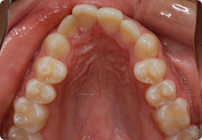

Caso: 20 años

Adulto: Clase II,

Mordida Abierta Anterior

Sin extracción

4 series de alambres:

.016″, .022″, .0215″ x .028″, .019″ x .025″ Trenzado;

Elásticos en cajas

Triangulares TP Rosa, Verde, Azul

Retenedores: Inferior Fijo

Tiempo de tratamiento: 16 Visitas